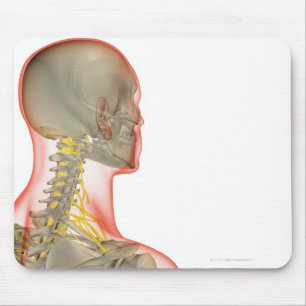

Mousepad Vértebras cervicais

PreçoR$ 77,30